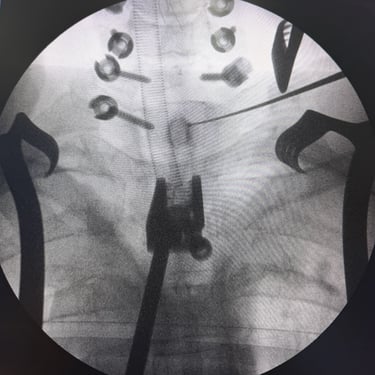

🧠Fractura vertebral lumbar osteoporótica en el adulto mayor: manejo con vertebroplastia percutánea.

Las fracturas vertebrales osteoporóticas en adultos mayores son una causa frecuente de dolor lumbar incapacitante. La vertebroplastia percutánea es un procedimiento mínimamente invasivo que permite estabilizar la vértebra afectada mediante la inyección de cemento óseo, logrando alivio del dolor y recuperación funcional temprana en pacientes seleccionados.